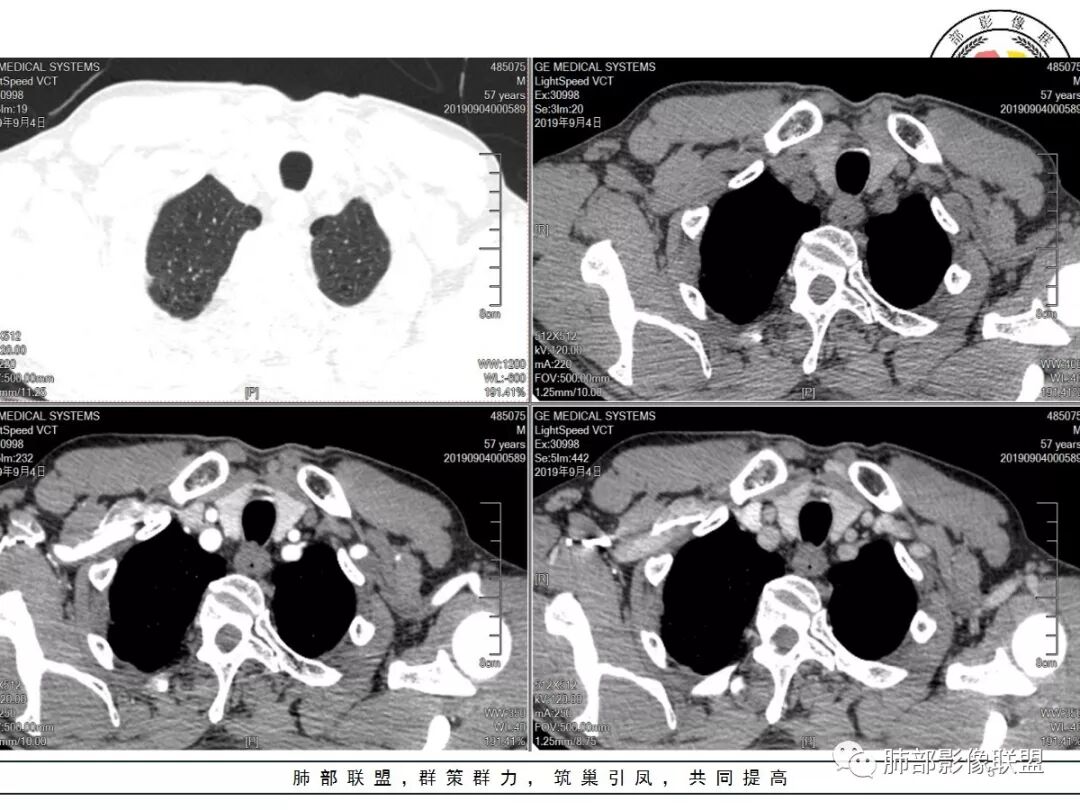

双肺尖斑片状影及结节影,边缘平直为主,边缘可见胸膜牵拉,考虑结核,鉴别诊断腺癌,本病特点,多灶性,多态性,胸膜牵拉线纤细。

右上肺病灶,边缘平直,有卫星灶,强化不明显,考虑结核可能大

结核。右上肺结节密度均匀轻度强化,结节边缘清晰有小分叶,周围细长软毛刺,有卫星灶。左上肺近纵隔类似片状结节。

理由:两肺尖都有小结节影(多发)

右肺尖结节边缘可见卫星灶,结节边缘平直凹陷、长毛刺,外观上有炎性结节的特点

增强扫描右肺尖结节强化不明确,但左肺尖后段结节出现了典型的环形强化